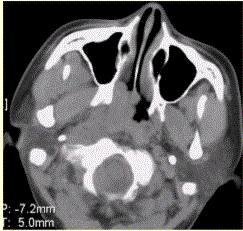

问题 患者男,45岁,鼻塞、涕中带血2周。查体颈部淋巴结增大。专科检查发现,鼻咽腔黏膜肿胀,左侧咽隐窝消失。CT表现如下图。 为明确诊断,应首选的检查为

选项 A.X线平片 B.CT检查 C.MRI D.DSA E.鼻咽活检 F.实验室检查

答案 E